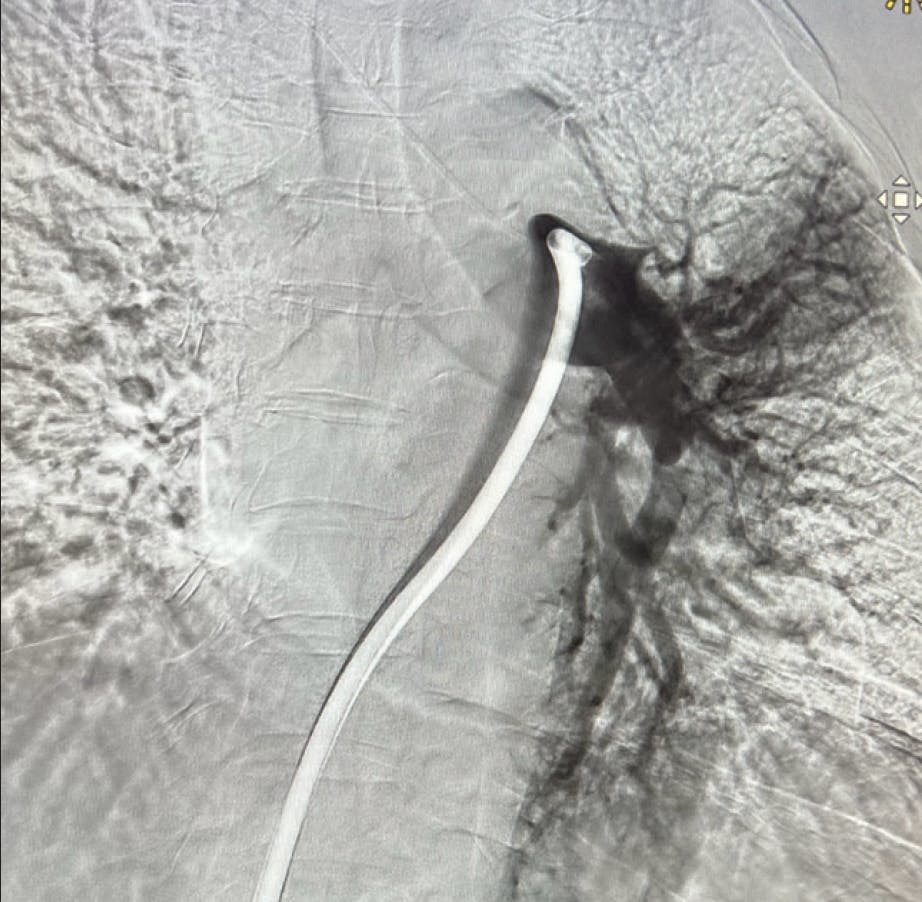

A patient in her early 40s with history of PE, severe obesity, hypertension, and iron deficiency presented to the ED with extreme shortness of breath. CT scan showed a saddle PE extending down the right PA in addition to several small distal thrombi; the thrombus extended to the PA bifurcation, almost completely occluding flow to the segmental arteries throughout the right lung (Figure 2).

Figure 1. Left lobe initial angiogram.

Figure 2. Right lobe initial angiogram.

On the left, there was thrombus in the proximal left pulmonary artery (Figure 1). Initial evaluation showed stable hemodynamics except for tachycardia, with a HR of 115 bpm, and revealed BP of 145/110 mm Hg, mild tachypnea, and 98% saturation on 2 L of oxygen. The patient had an RV/LV ratio of 1.4, indicating right heart strain. An echocardiogram showed mildly dilated right ventricle and mild systolic dysfunction, an estimated systolic pressure of 50 mm Hg.